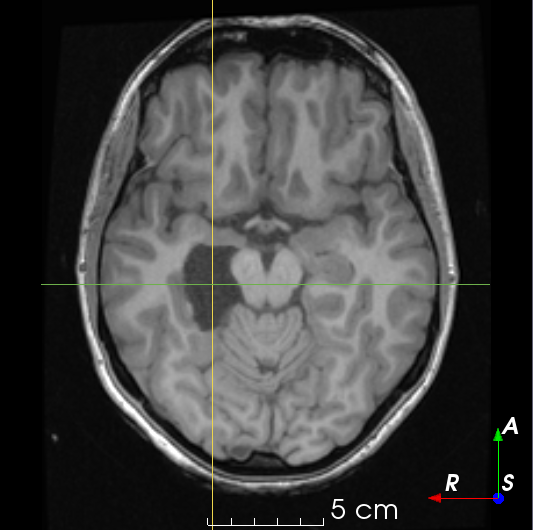

Refer to caption

Figure 5: Resection simulations 𝑿Rsubscript𝑿𝑅\bm{X}_{R} generated using our method.